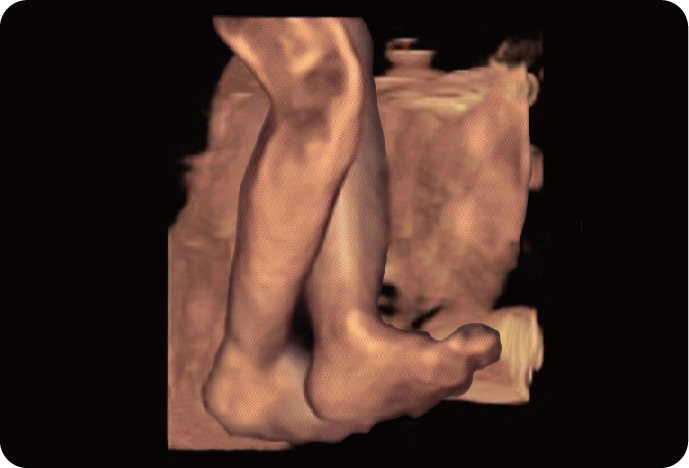

4D Объемный